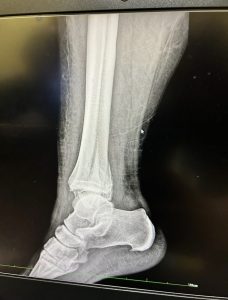

While serving on a medical mission in Guatemala in March 2024, Nikki sustained a serious ankle fracture—an injury that left her suddenly immobile, uncertain, and afraid. As an ICU nurse at Regions Hospital in the Twin Cities of Minnesota, she understood the medical realities of trauma, but that knowledge didn’t remove the emotional weight of becoming a patient herself.

In that vulnerable moment, Nikki knew she wanted Dr. Peter Cole—Chief of Orthopaedics at Regions Hospital and founder of Scalpel At The Cross—to be her surgeon.

From the very first appointment, something shifted. Nikki recalls feeling an overwhelming sense of reassurance—I’m going to be okay. When she was eventually told she was fully healed, the tears returned, this time not from fear, but from gratitude. She had walked through pain and come out restored, supported by a surgeon who treated more than just her injury.